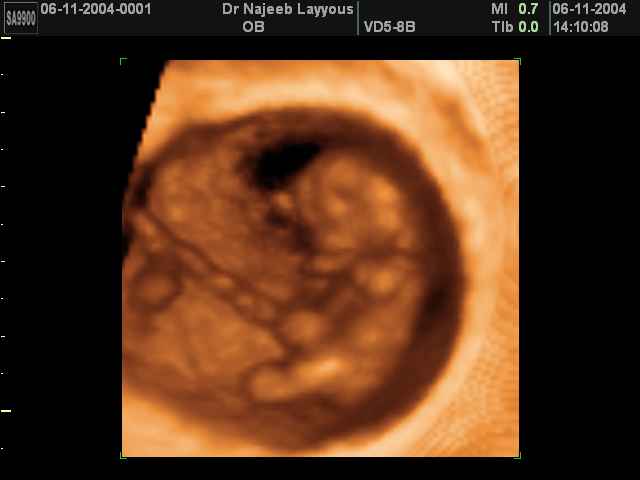

3D First Trimester Ultrasound Scan Photos ( Early Pregnancy Ultrasound Photos ) | Dr N Layyous

3D First Trimester Ultrasound Scan Photos